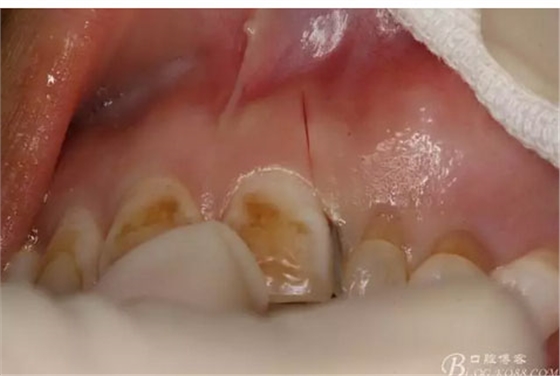

圖2.術(shù)前口內(nèi)像,左側(cè)乳Ⅱ、Ⅲ滯留,頸部楔形缺損,探針不敏感。左側(cè)乳Ⅱ、Ⅲ唇側(cè)粘膜膨隆,表面結(jié)節(jié)狀,捫診質(zhì)地堅(jiān)硬,無(wú)波動(dòng)。